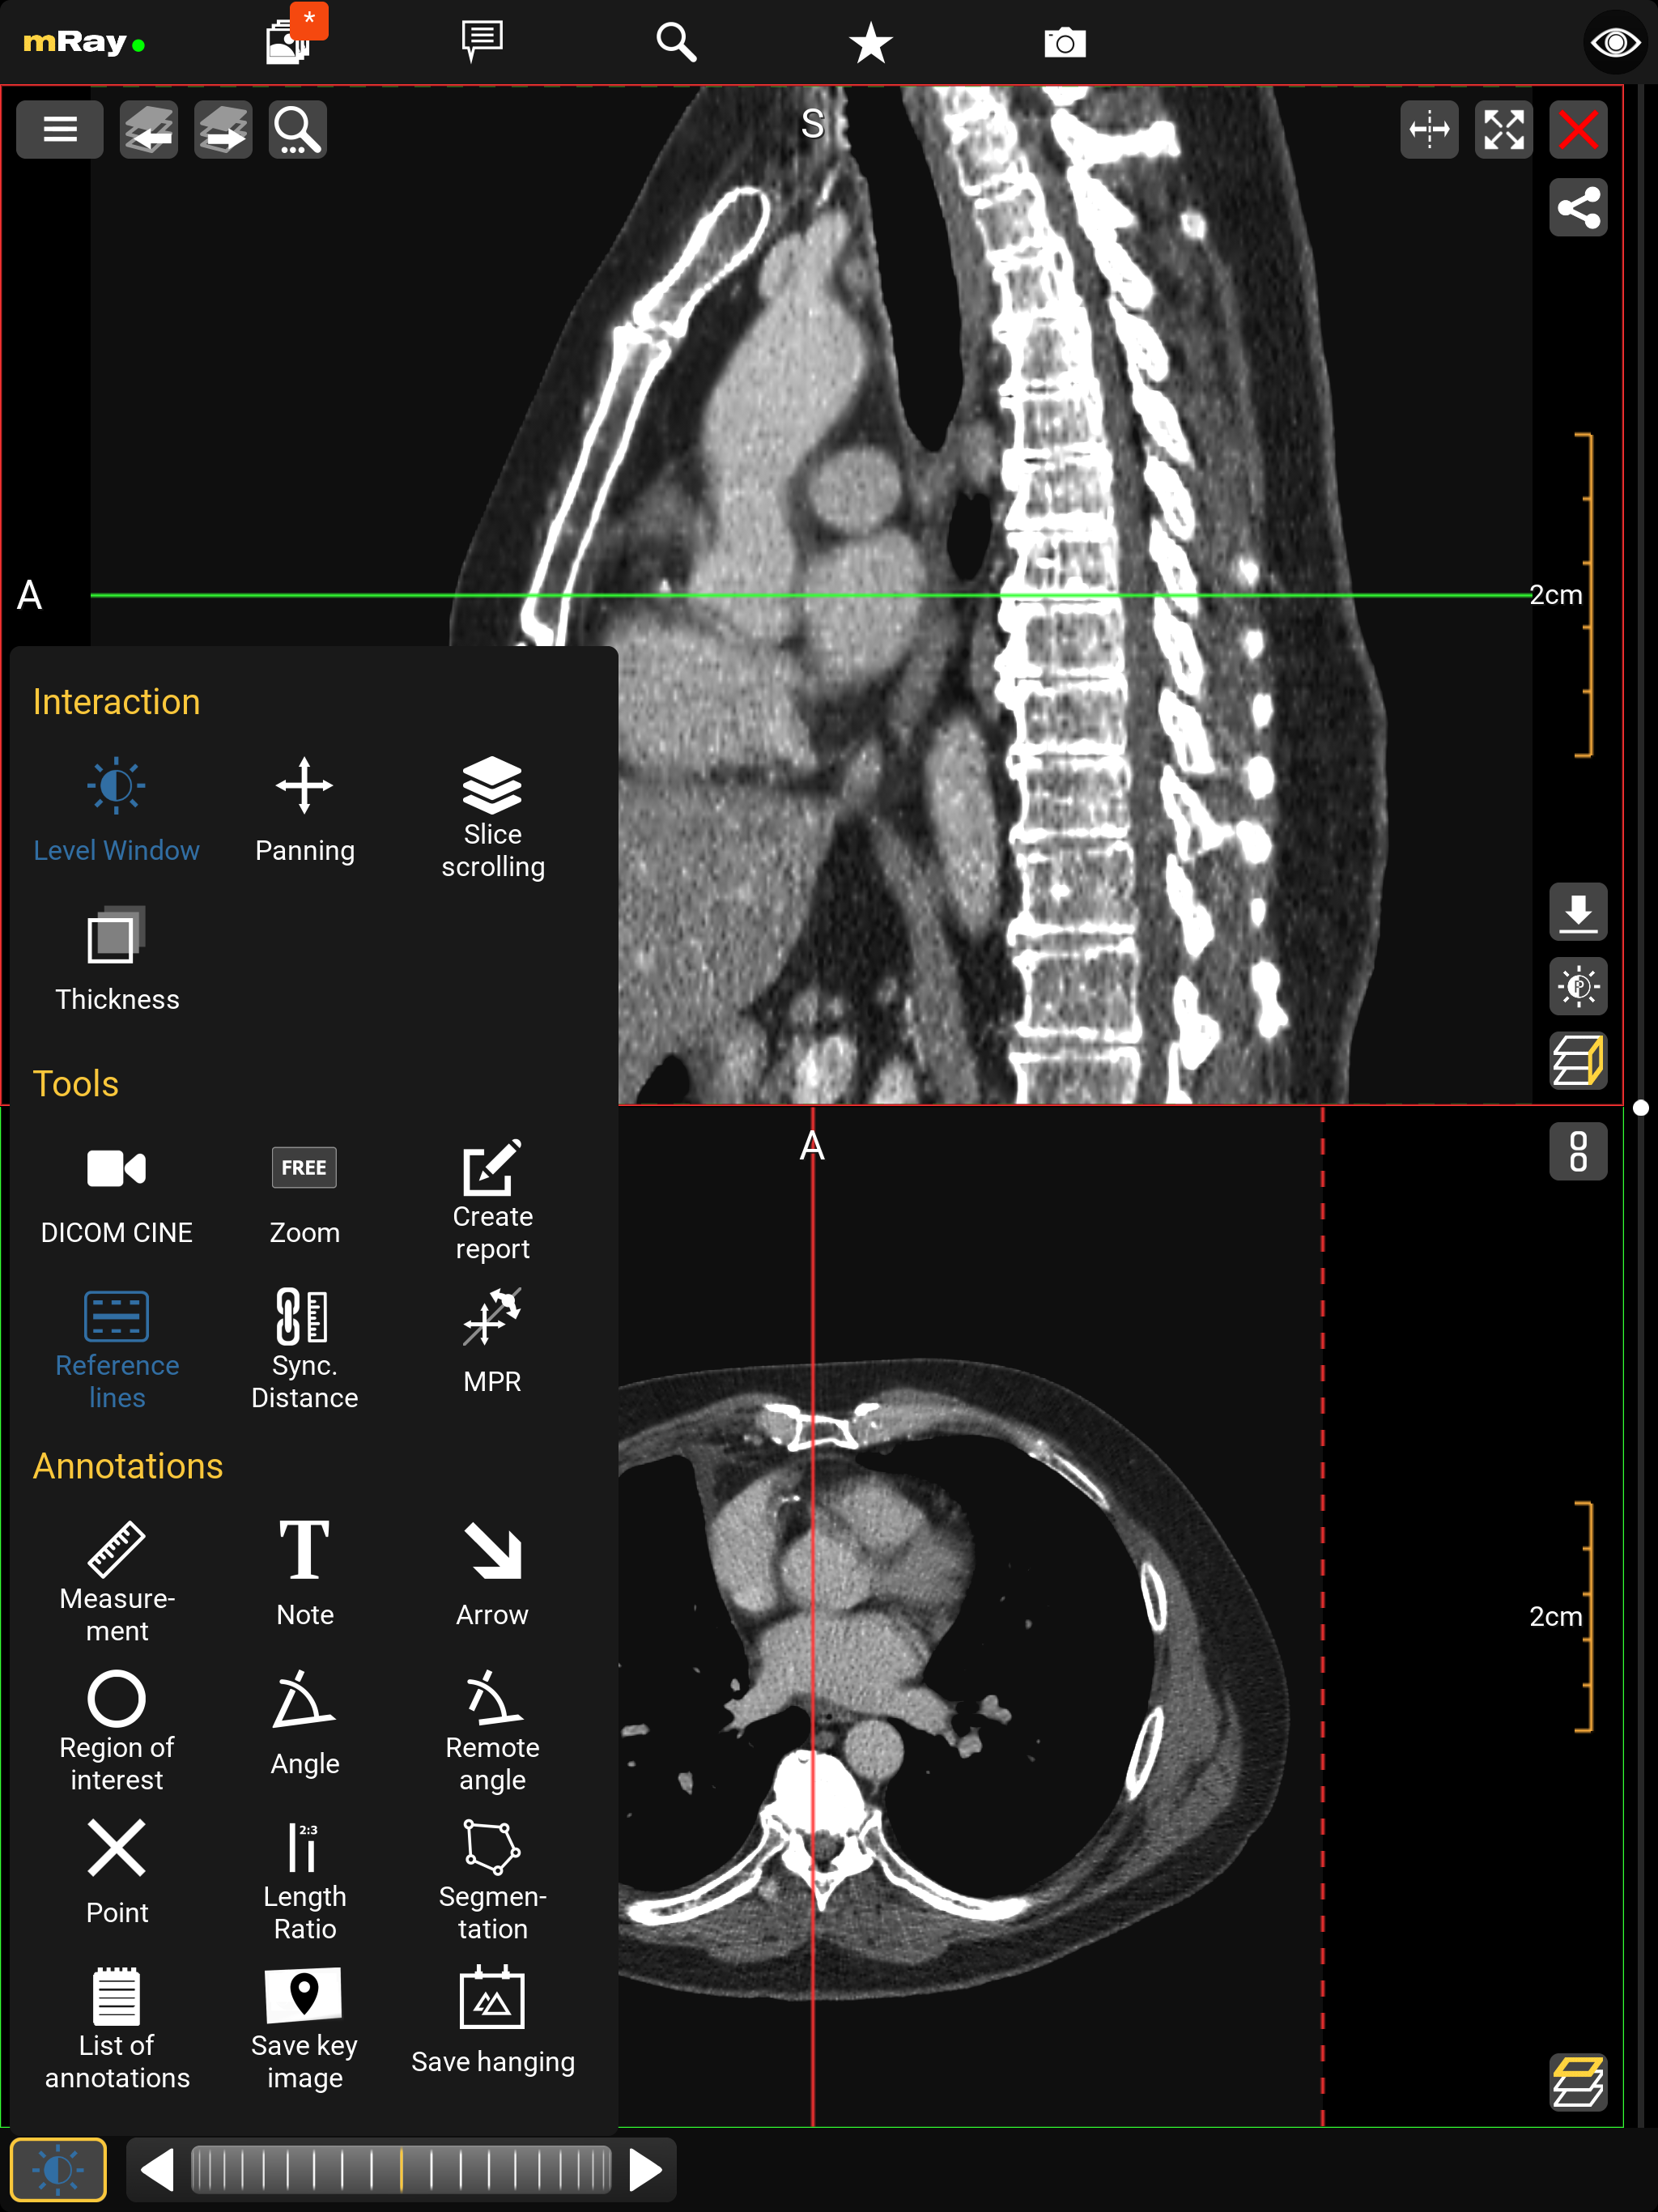

10.4. MPR Views

The MPR views allow you to open up multiple views at once ([abbr-mpr] View). Following screenshot shows the MPR view:

The Screenshot shows the original view of a dataset, the locally computed reconstructions (MPRs) and information to the viewed dataset.

-

Add more views here

.

The maximum number of views is 2 on smartphones and 4 on tablets.

Temporarily display view in a fullscreen state and back to previous state using maximize

.

The maximum number of views is 2 on smartphones and 4 on tablets.

Temporarily display view in a fullscreen state and back to previous state using maximize  and minimize

and minimize  icons.

icons. -

Indication of the current view direction in relation to the original image stack. You can change the view direction by pushing this button

.

. -

Use this button

to synchronize with the active view.

See Synchronized Views for more details.

to synchronize with the active view.

See Synchronized Views for more details. -

Shows the reference lines depending on the other opened views. These can be configured in the Toolmenu

You can change the perspective with the MPR perspective button (Point 2). This allows you to switch between axial, sagittal and coronal. The button in the top right corner (Point 1), allows you to open or close a view. If there is more than one view, a button to synchronize view adjustments will appear (see Synchronized Views). In order to interact with a view you have to select the appropriate view first. Therefore tap on the view. The selected view will be highlighted.

10.5. Toolmenu

You can select the following tools from the toolmenu:

-

Interaction

-

Level Window: With the level window tool you can modify the grayscale values and brightness of the view (Viewcontrol).

-

Panning: The panning tool allows you to pan, increase and decrease the size of the image. This tool is selected by default

-

Slice scrolling: You can scroll through the slice images via slice scrolling (see Interactionbar and Scrollbar). Scrolling happens via vertical movements on the image with the left mouse button pressed or by touch.

-

Thickness: Maximum intensity projection (MIP). View multiple slices at once (slices are superimposed). A maximum of 11 slices can be superimposed on each other.

-

-

Tools

-

Zoom: Zoom the image in and out in the preselected 'FREE' mode. By tapping the tool it will zoom the image to one of the prefabricated zoom levels in the following formats: 1:1, 1:2, 1:4 and 'FREE'.

-

Create report: Creates a structured report draft. See Report workflow for more details.

-

Reference lines: Switch between the different modes for displaying reference lines

-

MPR Display all MPR views of active dataset and enable plane control by dragging reference lines. (Arbitrarily oriented MPR)

-

SyncAlign Automatically align the patient position of one or more of the available datasets. (Synchronized Alignment)

-

Volume Rendering Visualize the active view’s dataset as a 3-dimensional volume. (Volume Rendering)

-

Annotations

-

Measurement: Create measurements on a slice of the image data set.

-

Note: Place a note on a slice of the image data set.

-

Arrow: Place an arrow on a slice of the image data set to highlight important regions.

-

Region of interest: This tool allows to mark a region of interest with an elliptical selection which shows information about the selected region imagedata.

-

Angle: Place an angle measurement on a slice of the image data set.

-

Remote angle: Allows to measure an angle (like the angle tool) between two lines.

-

Point: Place a cross on a slice of the image data set.

-

Length ratio: Show the length ratio between two lines.

-

Segmentation: Create a manual segmentation.

-

Save keyimage (to PACS): Saves the current view with all Annotations. The original dataset will not be touched. Optionally the keyimage will be uploaded to the PACS if your license supports the 'PACS upload' and it is properly configured.

-

Save Hanging: Save actual slices position and orientation from all view for future use.

-

List of annotations: Contains all annotations you added to the image. By long pressing an annotation in the list, more options such as multi-select, rename and delete will appear.